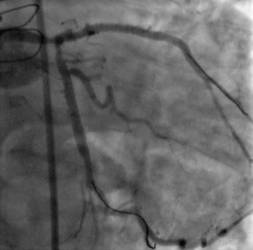

Se trata de un procedimiento que elimina las obstrucciones existentes en las arterias coronarias. Los doctores Juan Vicente Herrero Vilar y Eva Rumiz González, especialistas de la Unidad de Hemodinamia y Cardiología Intervencionista del Hospital Quirónsalud Valencia

, nos detallan esta técnica: "El dispositivo llamado Rotablator está basado en una pequeña fresa u oliva impregnada en partículas de diamante que tiene una rotación de 160.000 revoluciones por minuto y es capaz de pulverizar la obstrucción respetando las estructuras normales de la arteria. Sin esta técnica es imposible en muchos casos el implante de un stent, ya que al tratarse de obstrucciones con alto contenido de calcio impiden su avance dentro de la propia arteria".

Para poder entender su utilidad debemos tener en cuenta que una de las mayores dificultades a las que se enfrentan los especialistas a la hora de colocar un stent reparador de una lesión coronaria son las zonas calcificadas, que dificultan la entrada del propio stent en la arteria. Partimos del hecho de que el 95% de los pacientes con obstrucciones arteriales son tratados mediante angioplastia coronaria e implante de stent. Sin embargo, entre ellos, se dan casos con un grado de calcificación de las obstrucciones tan alto que el acceso se hace realmente complicado. Y es precisamente en estas ocasiones cuando la aterectomía rotacional se hace más útil, e incluso necesaria, ya que el Rotablator pulveriza las placas calcificadas, dejando intactas el resto de zonas de la pared artificial, y dejando el camino libre para el paso del stent.